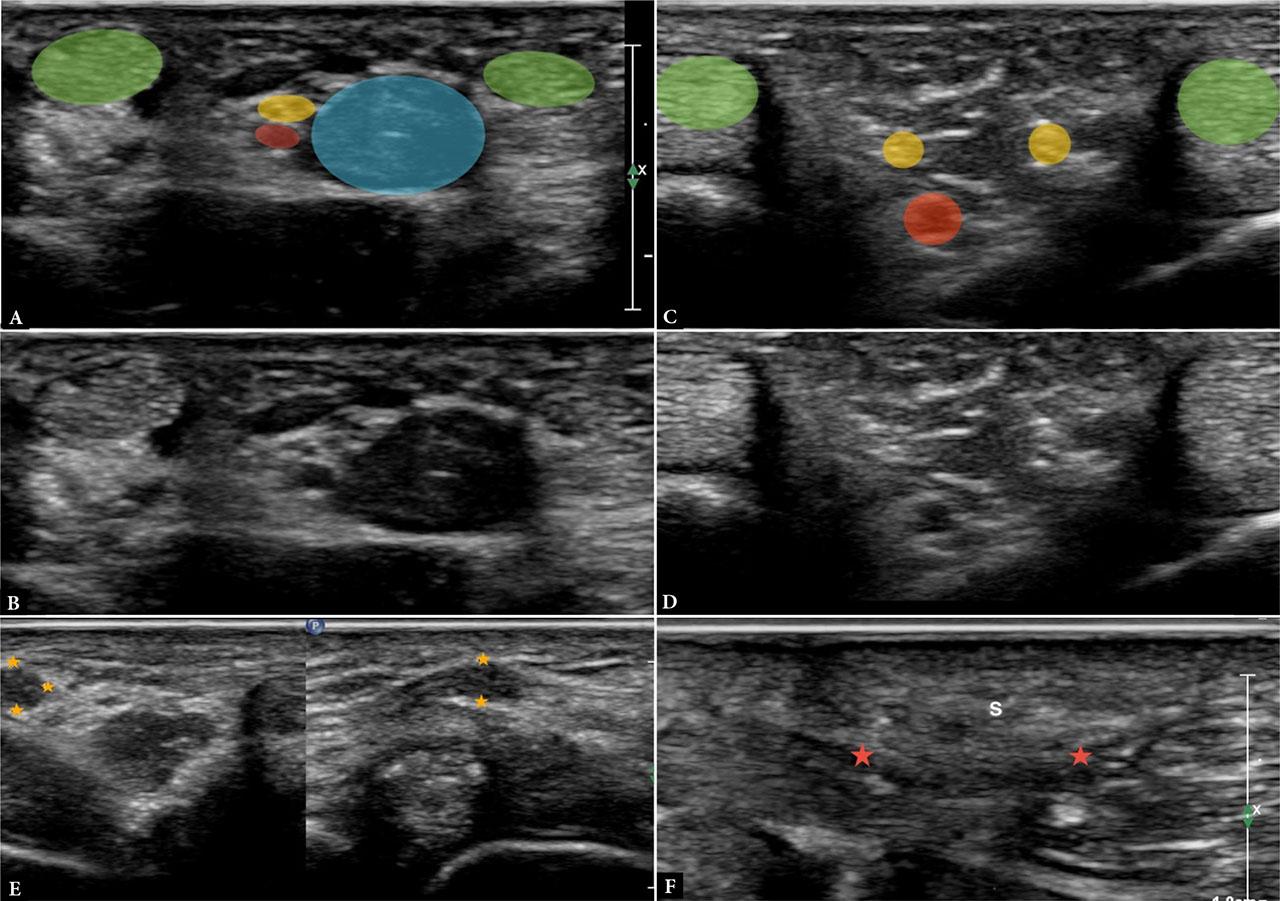

Digital nerve injury is a frequent consequence of penetrating trauma or surgical laceration, and sonography can detect discontinuity, neuroma formation, or focal thickening. Using high-frequency probes, paired neurovascular bundles can be identified adjacent to the flexor tendons with minimal transducer pressure. Scanning is initiated at the volar base of the finger along the flexor tendon sheaths, lateral to the digital arteries, and the neurovascular bundles are then followed distally alongside the tendons. The standoff pad or generous application of gel helps maintain acoustic coupling while avoiding excessive pressure, particularly when evaluating digital nerves near the fingertips(17,18) (Fig. 8).

Images A and B demonstrate the common digital nerve (yellow circle) at the level of the metacarpal head, with the lumbrical muscle (blue) between the flexor tendons (green). The red circle marks the digital vessels. Images C and D show the ulnar and radial branches of the digital nerve (yellow circle) as they course along adjacent fingers. The flexor tendons of the respective fingers can also be seen (green). Image E demonstrates a neuroma in two orthogonal planes in continuity with a common digital nerve (asterisk). Image F shows entrapment of the ulnar digital nerve (red asterisk) of the thumb within scar tissue (S) in a patient following pulley release